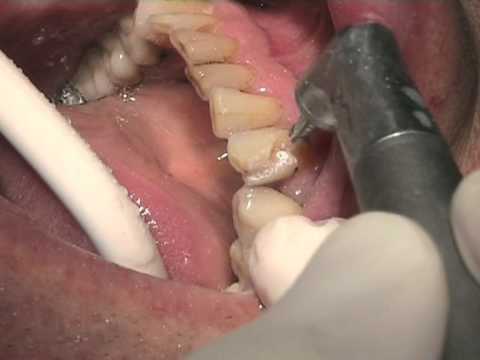

Carie de collet Laser KAVO.mpg :

comment soigner carie